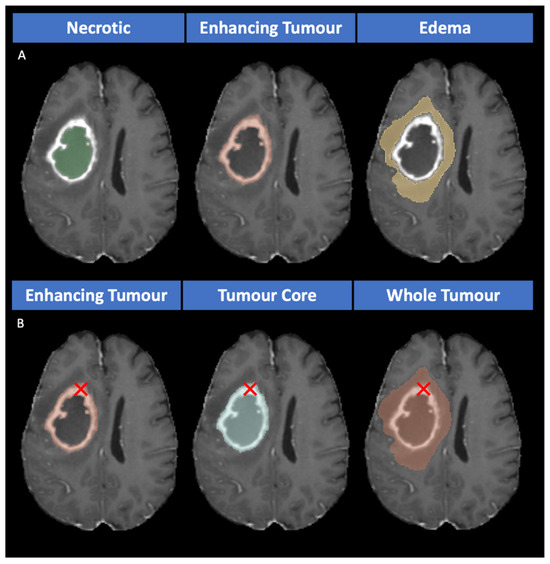

3.3.1. Segmentation Approaches